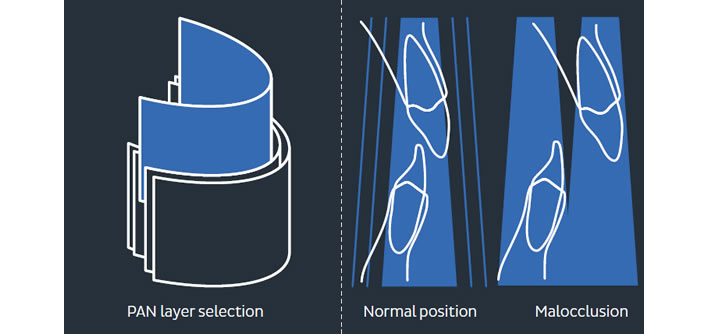

Uređaj koji koristimo prilikom slikanja ortopana snima 5 slojeva snimke unutar jedne ekspozicije tako da se dobije što bolji prikaz čeljusti i zubi.